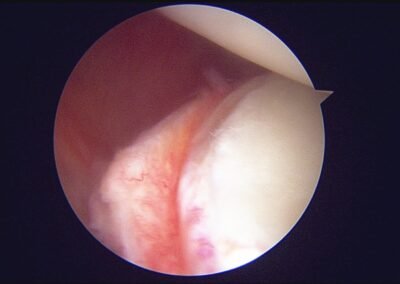

GalleryShoulder rotator cuff repair Meniscus root repair Meniscus repair Bankart repair for recurrent shoulder dislocation ACL reconstruction Machines Instruments